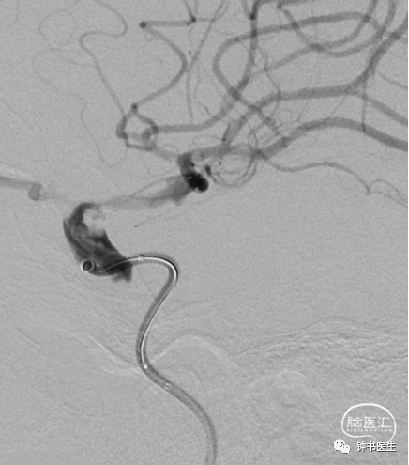

病例2

患者,女,78岁

突发右侧肢体无力5小时入院

高血压病20余年,予培哚普利降压。有糖尿病史4年,予阿卡波糖控制血糖。

BP:188mmHg/89mmHg

神清,语对答切题,右侧鼻唇沟偏浅,右上肢肌力2级,右下肢肢体肌力2级。

神经重症治疗思路

血压:超时时窗(降压)

原位狭窄(预防血压过低)

没有代偿(预防血压过低)

入院BP:188mmHg/89mmHg

目标血压:110-130mmHg

超时时窗(深度镇静镇痛)

原位狭窄(替罗非班、双抗)

2017-7-6 CT

2017-7-7 CT

2017-7-12 CT